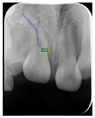

根尖片示:11自根中向远中弯曲约35°,属Ⅱ类弯曲牙,牙根发育至Nolla9期,21牙根发育至Nolla9期,腭侧见两颗正置锥形多生牙;12、22牙根发育至Nolla9期。

患者初诊时根据恒牙发育Nolla分期诊断该患者11、21、22迟萌,其可能原因与腭侧多生牙、11牙根弯曲及可能患有颅骨锁骨发育不全综合征相关。

弯曲牙是指牙齿在发育过程中受损伤,牙冠与牙根的线性关系发生转折,使牙齿出现弯曲的现象。弯曲牙上颌多见[3,4],最常发生于上颌恒中切牙[5] 。前牙弯曲的最主要成因是恒牙胚发育时的乳牙外伤[4]。此外,异位牙胚发育、乳牙拔除、囊肿形成、根管感染、萌出空间不足、瘢痕组织、面裂、解剖结构的异常、药物、精神因素和系统性疾病等,也可导致前牙弯曲[6,7,8]。

关于弯曲牙的诊疗,尚无统一的分类标准及治疗规范。有学者结合弯曲牙根发育程度和萌出潜力,模拟弯曲牙牙冠复位后牙根与牙槽嵴的包容关系,以及弯曲牙复位技术的实施难度,将弯曲牙分为4类[9]并提出相应治疗策略。该分类如下:

I类:牙冠或冠根轻度弯曲(<30°),垂直向埋伏,患牙牙根发育与正常同名牙近乎同步,并且具有萌出的潜力(X线片评估牙囊、牙根及牙周组织、根尖牙乳头组织无明显异常)。

Ⅱ类:牙冠或冠根轻、中度弯曲(30°~60°),垂直向阻生,患牙萌出迟滞于健康同名牙,牙根形态正常并且发育仍未完成。可采用诱导干预方法。通过外科开窗助萌或局部固定矫治器开辟患牙萌出间隙,定期观察患牙自然萌出情况;待患牙萌出后修复牙冠形态,或正畸平整牙列。

本例患者11属于Ⅱ类弯曲牙,21未见牙根弯曲。对11、21采取早期矫治手段,通过外科开窗助萌开辟患牙萌出间隙,定期其自然萌出情况,必要时利用矫治器牵引患牙使其萌出。该患者于笑气辅助局麻一次性拔除上颌前牙区多生牙后,对11、21进行开窗助萌,观察4个月后因11仍无法自行萌出,因此对其进行正畸牵引,6个月后11完全萌出,并与41形成浅覆牙

浅覆盖关系。